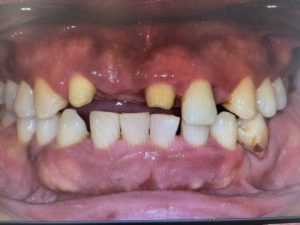

最近拝見した患者様の中でかなり重症だった方です。

写真は正面観で、前歯ももちろん瀕死の状態でしたが、奥歯がもっと重症で、食いしばりが酷いために歯周病が悪化して4本も抜かなければいけない状態でした。

そして抜くだけではダメで、下がってしまった噛み合わせを挙上していく必要がありました。